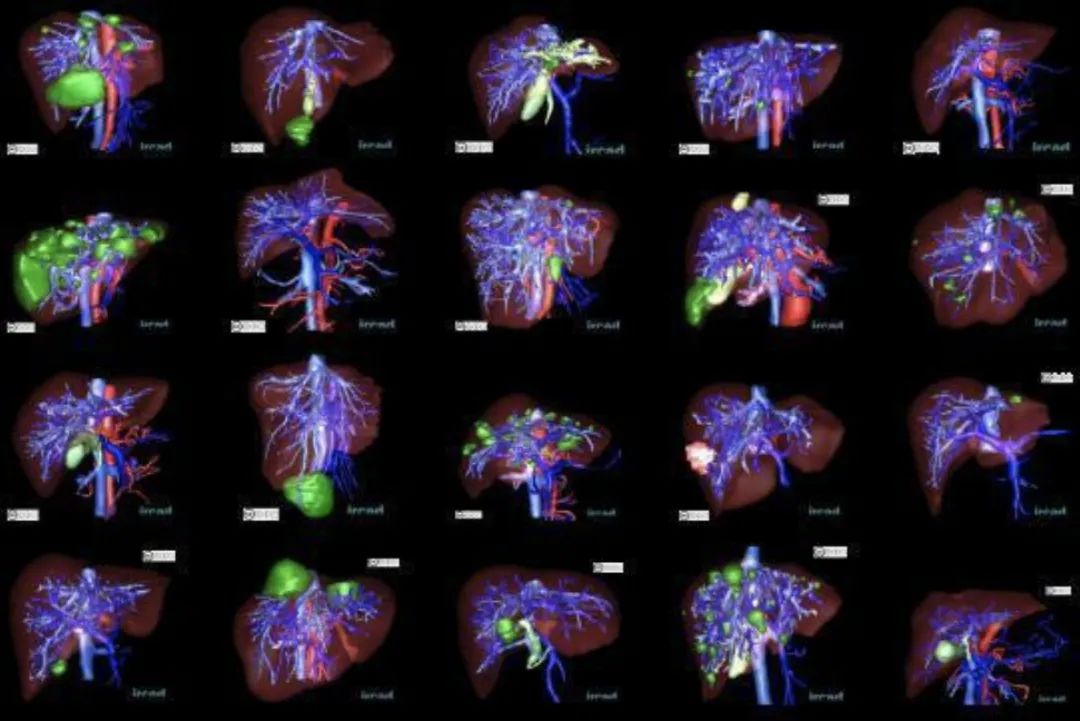

重磅干货,第一时间送达3D-IRCADB 脏器分割数据集

数据集链接:http://m6z.cn/6x5OSn

3D-IRCADb-01 数据库由 10 名女性和 10 名男性 75% 的肝肿瘤患者的 3D CT 扫描组成。20个文件夹对应20个不同的患者,可以单独下载也可以联合下载。下表提供了图像信息,例如肝脏大小(宽度、深度、高度)或根据 Couninaud 分割的肿瘤位置。它还表明肝脏分割软件可能遇到的主要困难是由于与邻近器官的接触、肝脏的非典型形状或密度,甚至图像中的伪影。